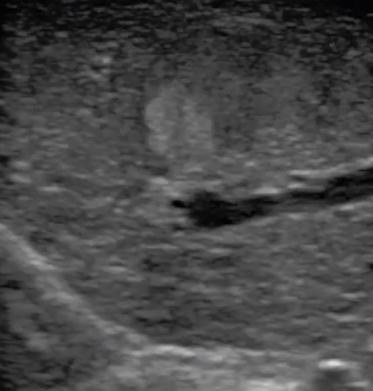

3  腹腔鏡超聲探頭

腹腔鏡超聲是超聲技術(shù)和腹腔鏡技術(shù)的融合,腹腔鏡超聲降低了對超聲探測深度的要求。由微小切口進(jìn)入手術(shù)部位,多角度彎曲可選擇,降低手術(shù)難度及風(fēng)險(xiǎn);與受檢組織器官直接接觸,有效避免氣體干擾。

應(yīng)用科室:麻醉科、手術(shù)室、普外科、泌尿外科、婦產(chǎn)科、腫瘤科、介入科等

腹腔鏡下 肝臟占位